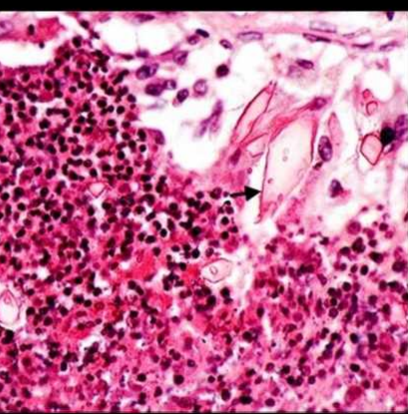

Синдромът на Loffler е с доброкачествено протичане. При синдрома на Loffler лезиите са преходни и няма васкулит, фиброза или некроза( липсват ). Стените на алвеолите са задебелени ( Еозинофили ).

- Кристали на Шаркот – Лайден

- Спирали на Кършман